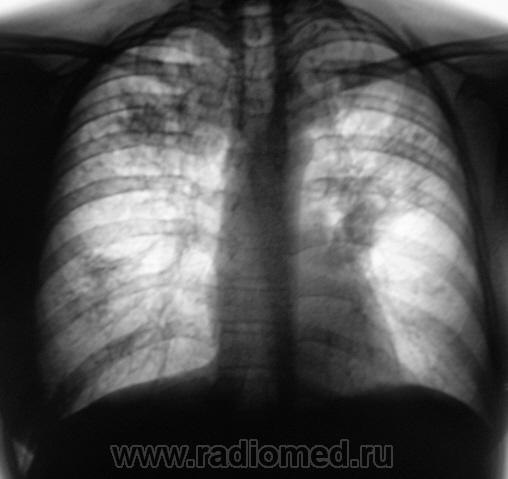

"Полезли" в электронный архив. Нашли флюорограмму за 2007 год (слева) и 2008 год (справа две).

Флюорограмма за 2007 год была оценена, как "норма". Изображение 2008 года - было отмечено локальное снижение прозрачности легочной ткани на уровне 2 ребра справа, на фоне чего дифференцируются отдельные очаговоподобные тени. Была рекоменндована "консультация терапевта" и полное клиническое обследование. Однако "сие" - рекомендации рентгенолога не были приняты к сведению.